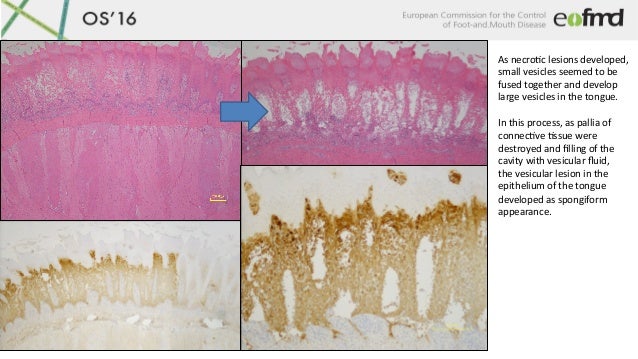

14. 14. OS16 As necroLc lesions developed, small vesicles seemed to be fused together and develop large vesicles in the tongue. In this process, as pallia of connecLve Lssue were destroyed and filling of the cavity with vesicular fluid, the vesicular lesion in the epithelium of the tongue developed as spongiform appearance.